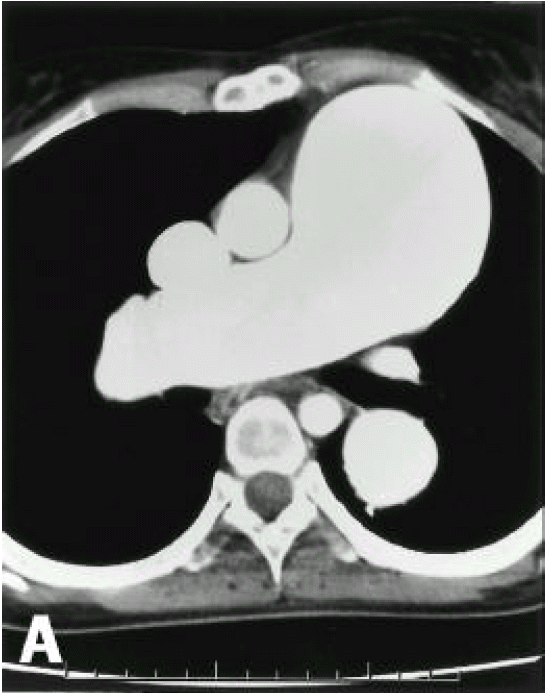

A diagnosis of Eisenmenger syndrome was made. The base-line study for heart-lung transplantation, including chest computed tomography (CT), cardiac catheterization and coronary angiography were undertaken. Chest CT scan with contrast revealed markedly dilated pulmonary trunk and both pulmonary arteries (Figure 2A), a concave disfigurement of the left side of the ascending aorta and nearly total occlusion the ostium of the left main coronary artery that was retrogradly filled with collateral circulation from the right coronary artery (Figure 2B). That was suggestive of compression of the left side of the aorta and the left main coronary artery together by the pulmonary trunk passing by the ascending aorta’s left side. Cardiac catheterization revealed PASP of 105 mmHg, Qp/Qs of 1 and Rp/Rs of 1.4 (Figure 3), which mean no remaining shunt but much aggravated pulmonary hypertension compatible with Eisenmenger syndrome compared with preoperative data. The coronary angiography showed normal right coronary artery and the collaterals that came out from the conus branch to mid-left anterior descending artery (LAD) and that from the distal right coronary artery to the left circumflex artery (LCX) and to the distal LAD, respectively (Figure 4, 5). Engagement of the left main coronary artery with the diagnostic coronary catheter was not available. On aortography, the left main coronary artery was not visualized with no stump, suggesting total occlusion of the ostium of the left main coronary artery (Figure 6). There was no other luminal lesion in the remaining part of the coronary artery system and the thoracic as well as the abdominal aorta.

Figure 2A, 2B.Figure 2A, 2B.

Chest CT scan with contrast. Markedly dilated pulmonary trunk and pulmonary arteries (Figure 2A). There are a concave disfigurement of the left side of the ascending aorta (closed arrow) and just beside, the focally occluded left main coronary artery (open arrow) that was retrogradly contrasted by collateral circulation from the right coronary artery (Figure 2B)

Figure 2A, 2B.